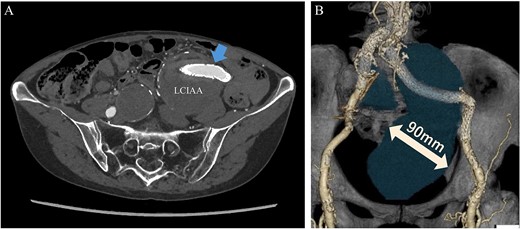

She underwent surgery under general anesthesia. A midline abdominal incision and an intraperitoneal approach were employed. The retroperitoneal space was accessed from the lateral side of the sigmoid colon to reach the CIA. The aneurysm was incised midway. The hematoma and coils were removed, and the stent graft was observed. The laparoscope was utilized to inspect areas obscured from direct view, such as behind the stent graft, to confirm that no type I or IIIb endoleak was present (Fig. 5). A type II endoleak was observed near the proximal neck of the stent graft, which was thought to be the cause of the aneurysm expansion. The IIAA was sutured with 3–0 monofilament, and the aneurysm was closed. The left ureter was close, and care was taken during suturing to avoid including it in the stitches. The operation took 177 min, and the patient was discharged on the tenth day postoperation. Follow-up CT at 7 months postoperation showed a reduction in aneurysm size (Fig. 6).

Laparoscopic view of checking for type I endoleak presence. SG, stent graft.

Postoperative computed tomography showing a reduction in aneurysm size. A—Preoperative image, B—7-month postoperative image.